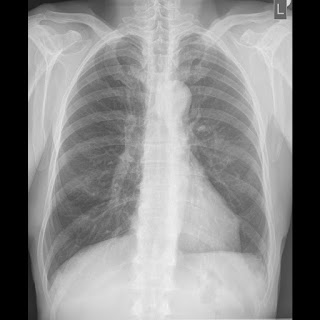

Foto: EPA/FRANCK ROBICHON, Privatna arhiva Foto: EPA/FRANCK ROBICHON, Privatna arhiva Foto: EPA/FRANCK ROBICHON, Privatna arhiva Srpski doktor raskrinkao teoriju zavere o koroni i sarinu autor: Božica Luković Zdravlje 11. nov. 2020. 11:33 > 16. jan. 2021. 11:01 0 Podeli vest: Koronavirus prate razne teorije zavere, koje utiču na to da ljudi ne nose maske i da se generalno ponašaju neodgovorno. Jedna od najapsurdnijih je da je virus zapravo bojni otrov sarin koji je među narod pustila Amerika. Srpski radiolog Aleksandar Ivković objasnio je zašto je to potpuno netačno. Podeli vest: Oglas Još u martu počele su da se pojavljuju informacije da korona ne postoji, već da je prvo na ljude u Kini, a zatim i na celu planetu, pušten bojni otrov sarin. Navodno su simptomi jako slični, kao i šteta po organizam.Recimo, ovo je jedna objava u kojoj se tvrdi upravo to. NIJE CORONA NEGO - SARIN !!! SVE JE LAZ!Ovo su za sada najpouzdanije informacije o prevari veka pod velom...Objavljuje Kravo u Četvrtak, 26. ožujka 2020. Oglas Ukratko, sarin su ispustili američki vojnici kada su imali vežbu u Kini. Simptomi su "nos koji curi, stiskanje u grudima - ubrzo nakon toga osoba ima poteškoće sa disanjem, gubi kontrolu nad telesnim funkcijama, pa povraća i mokri. Ovi simptomi se mogu uporediti upravo sa kovidom 19", tvrde pobornici ove sulude teorije.Srpski radiolog Aleksandar Ivković je na svom blogu "Ljudi i ostale laži" raskrinkao ovu teoriju zavere. Objavu prenosimo u celosti."Jedna od omiljenih teorija zavera je da ne postoji virus SARS-CoV-2 već se iz aviona ispušta gas sarin i da su svi u svetu udruženi da sakriju istinu, pa eto oni bez formalnog znanja uvek bolje znaju i oni su otkrili to. Ne očekujem da znaju kako izgleda trovanje sarinom. Zato ja znam.Pre par godina sam pisao neki rad o terorističkim napadima i njihovom delovanju na pluća. Među njima je obrađen i sarin. Hajde da uporedimo.Sarin je je organofosforno jedinjenje sa formulom (CH3)2CHO]CH3P(O)F. On je bezbojna, bezmirisna tečnost. Virus SARS-CoV-2 ima oko 5 miliona molekula u svojoj građi i RNK koja prenosi informacije koje virus nosi. Ali hajde, poklapa se bezbojno i bezmirisno. I jedno i drugo su u vazduhu.Sarin deluje na motorni ili parasimpatički neuron, SARS-2 na ACE-2 receptore koji se nalaze u plućima, crevima, mišićima, jetri, bubrezima a izaziva zapaljenja korteksa mozga. Ne poklapa se ništa.Sarin otpušta neuroprenosnik acetilholin koji prenosi impuls do mozga. Nakon toga enzim acetilholinesteraza razlaže acetilholin da bi se mišić opustio. Sarin remeti rad nervnog sistema tako što sa holinesterazom gradi kovalentnu vezu na mestima u kojim bi normalno acetilholin podlegao hidrolizi. Zbog ovoga se nervni impulsi kontinuirano prenose. Dolazi do naglog suženja zenica (na slici) SARS-2 se vezuje za ACE-2 receptore i prodire u ćeliju gde se multiplicira. Opet se ne poklapa ništa. Foto: EPA/FRANCK ROBICHON | Foto: EPA/FRANCK ROBICHON Početni simptomi nakon izlaganja sarinu su nos koji curi, stiskanje u grudima. Ubrzo nakon toga osoba ima poteškoće sa disanjem, gubi kontrolu nad telesnim funkcijama, pa povraća i mokri. Udisanje sarina ili dodir sa njim preko kože je jednako opasan. Čak i koncentracija pare je dovoljna da brzo prodire u kožu. Ljudi koji se izlože sarinu, a ne dobiju odgovarajući tretman mogu imati posledice za čitav život. Osnovno je simptomi nastaju naglo. Simptomi kovida-19 nastaju polako, iz dana u dan se menjaju i pojčavaju. Ne gubi se kontrola nad telesnim funkcijama. Žalim, ni slično.Kako izgledaju pluća nakon udisanja sarina? Trovanje počinje nekoliko sekundi nakon udisanja, naglo. Javlja se prvo edem disajnih puteva, onda suženje disajnih puteva, ako se ne leči dolazi do pucanja alveola. To se sve desi u roku od nekoliko minuta do par sati. Opet ni slično kovidu-19. Oglas Foto: Aleksandar Ivković | Foto: Aleksandar Ivković Sarin je bio u upotrebi u Siriji. Ovo su pacijenti koji su bili izloženi 2018 i 2019 i preživeli. Na prvom snimku nema nekih značajnih promena. Iskusno oko može da vidi znake edema disajnih puteva. Foto: Aleksandar Ivković | Foto: Aleksandar Ivković Kod ovog pacijenta se već vide promene ali i one nisu posebno značajne. Oglas Foto: Aleksandar Ivković | Foto: Aleksandar Ivković Ovo je 12 sati nakon udisanja, došlo je do značajnih oštećenja i pucanja alveola. Foto: Aleksandar Ivković | Foto: Aleksandar Ivković Ovo je kovid-19. Nema nikakve sličnosti sa nalazom nakon trovanja sarinom.Prosto vas molim da prekinete sa iznošenjem potpunih gluposti kao što je ova sa sarinom. Razumem da vas nebuloze privlače, ali ako vam je do njih gledajte filmove, tamo ih ima koliko god vam je volja.Time što negirate postojanje virusa to ne govori ništa o njemu, već samo o vama. Kako da vas iko shvati iole ozbiljno? Ozbiljnije priče se čuju od dece", napisao je radiolog.***Bonus video:https://www.youtube.com/watch?v=ufUqk8k_rA4Pratite nas i na društvenim mrežama:FacebookTwitterInstagram Aleksandar Ivković koronavirus sarin Pratite nas na društvenim mrežama: Koje je tvoje mišljenje o ovoj temi? Učestvuj u diskusiji ili pročitaj komentare Budite prvi koji će ostaviti komentar Pošalji komentar Pročitaj komentare (0)